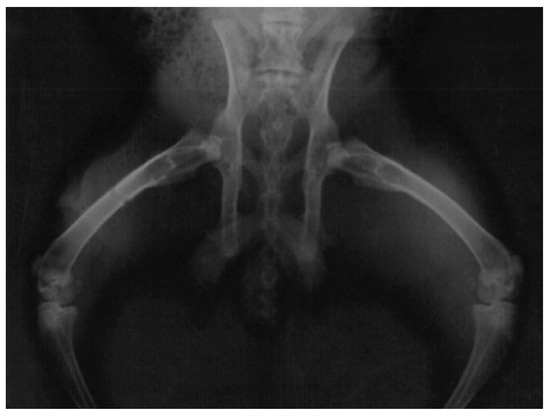

3.4. Radiographic Assessment